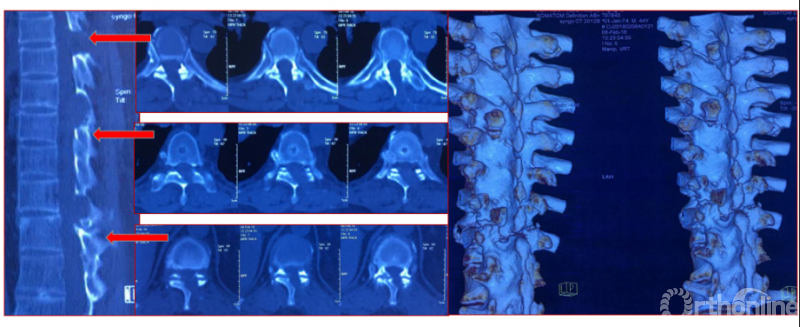

Case5:多节段胸椎后纵韧带钙化可视化治疗

影像学资料

术中资料

同一侧一次两个节段减压,择期对侧进行两个节段减压,两侧腹侧减压范围可达到硬膜囊360度环形减压效果。术后复查硬膜囊环形减压效果。关节突关节破坏较多,需长期佩戴支具固定,保证术后脊柱稳定性。

术后复查资料